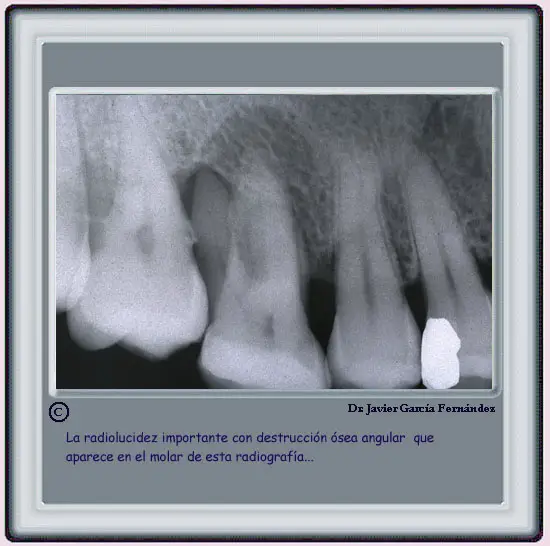

EXAMEN RADIOLOGICO

image261